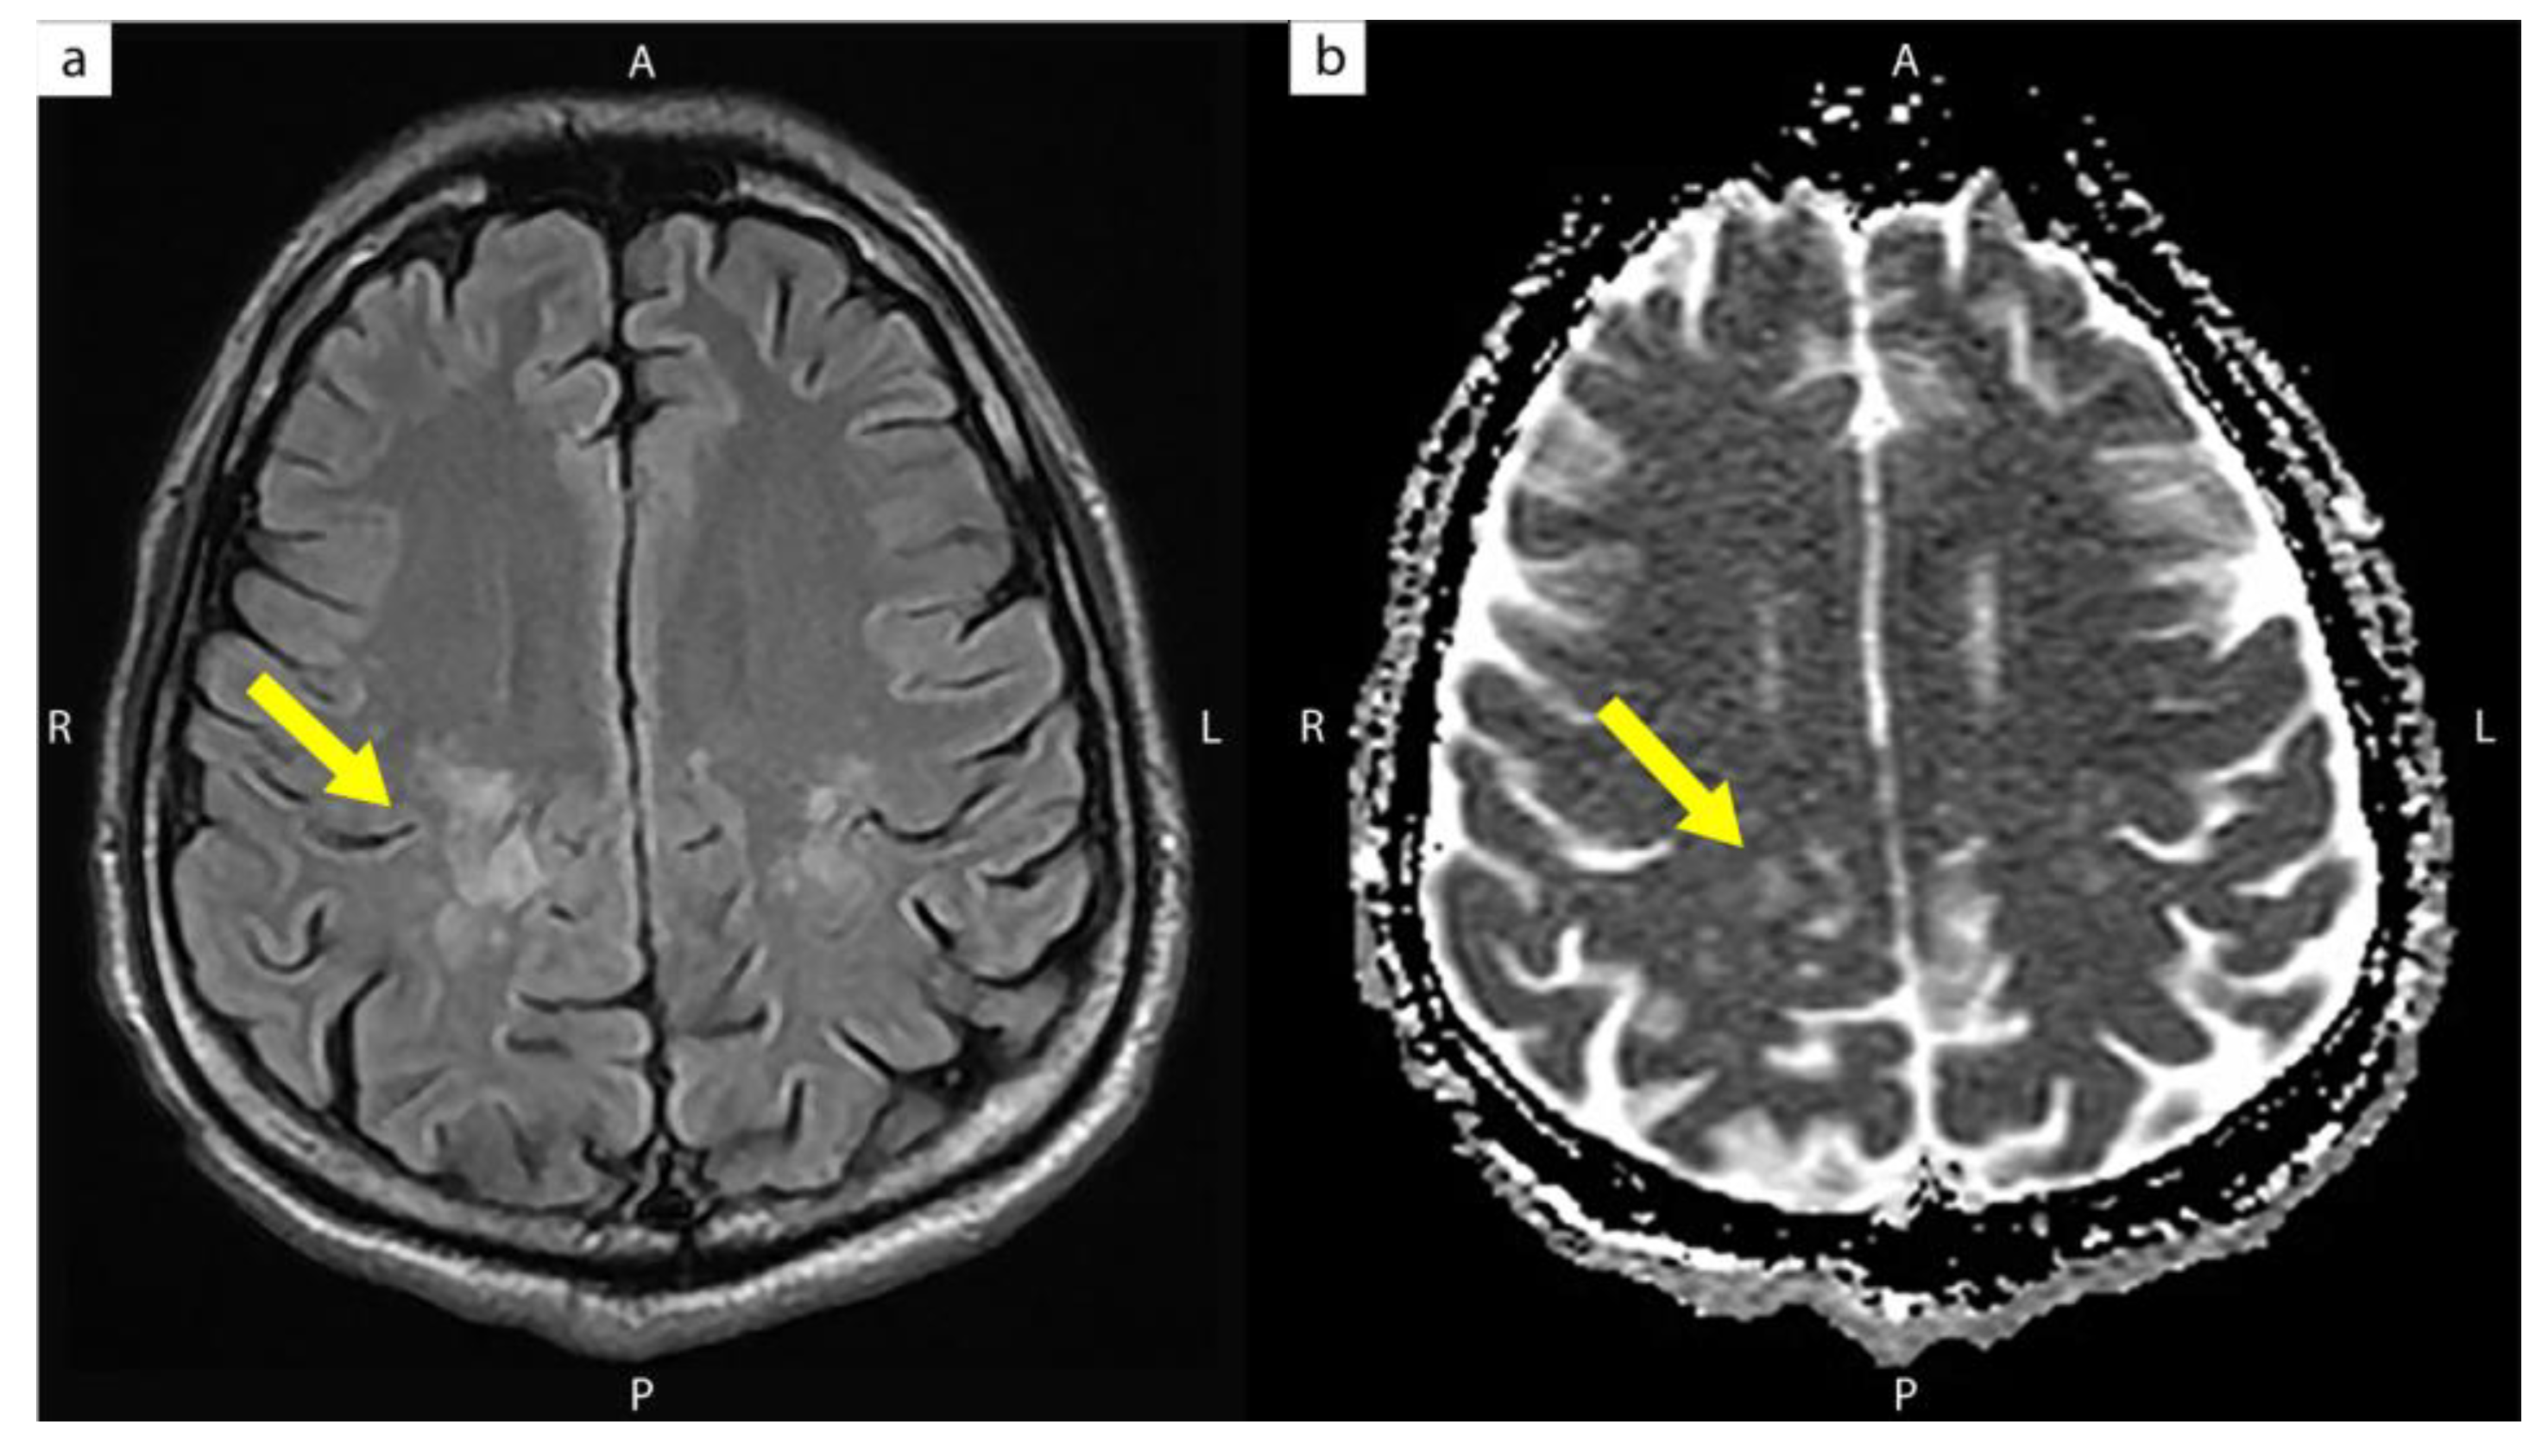

| The present case | 31/M | 4 | 109 | 586,300 | 113 | 3 months | CIDP with progressive quadriparesis (Unmasking IRIS) | High signal intensities over both the posterior corona radiata and centrum semiovale |